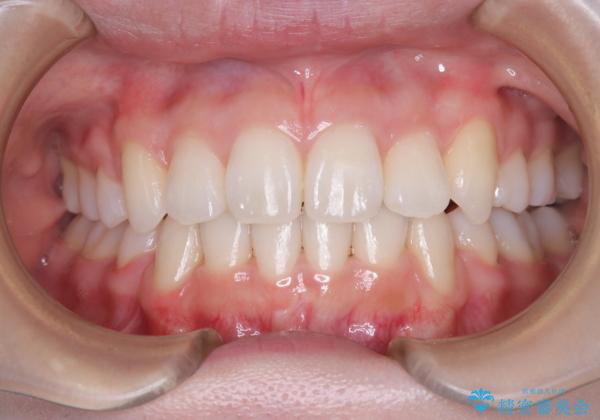

【審美ワイヤー】八重歯を治したい。

- 左上の犬歯の凸凹や正中のずれを主訴に来院されました。

凸凹を治すために、上下左右の小臼歯を抜歯してワイヤー矯正を行いました。

患者様には、顎間ゴムを使用していただくことで、2年という期間で治療を終了することができました。